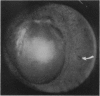

A case of intraocular paragonimiasis is reported in a 13-year-old Chinese boy. The disease manifested as repeated attacks of acute intraocular pain associated with panuveitis. A combination of inflammatory reaction and ocular findings mimicking both perforating and contusion injuries caused by the migration of the fluke within the eye characterises the infection. The living fluke was successfully extracted from the anterior chamber and identified as Paragonimus westermani.